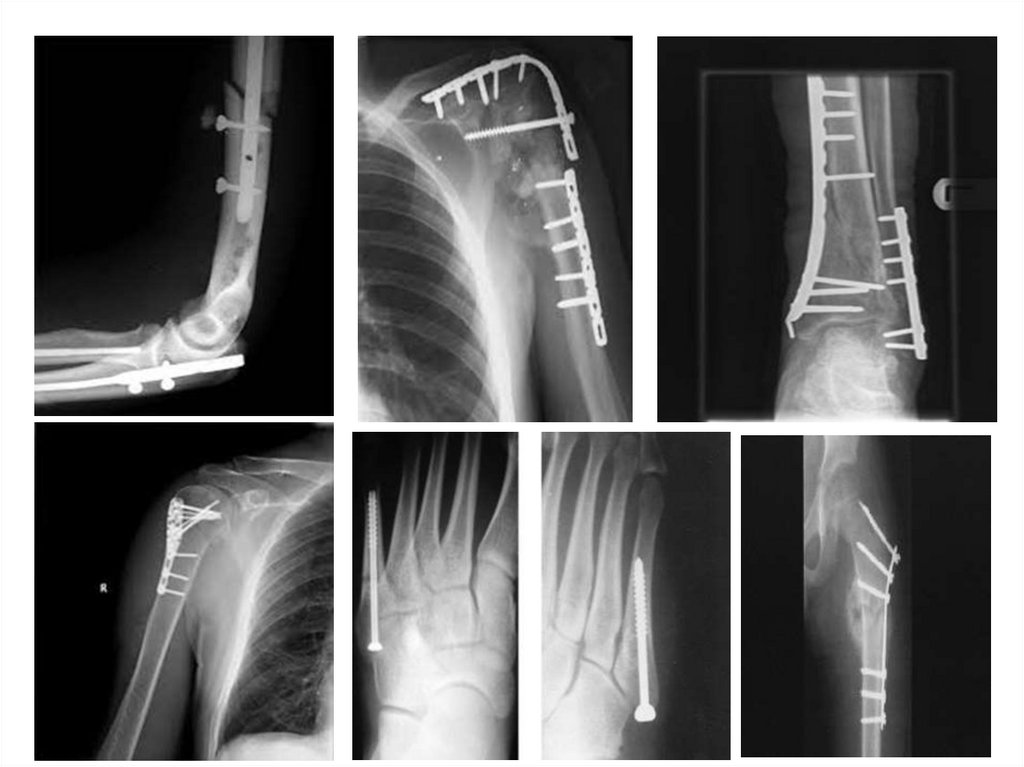

Остеосинтез

• Экстрамедуллярный

• Интрамедуллярный

• Компрессионно-дистракционн

ый

• Спицами и винтами

• Шовным материалом

72.

Экстрамедуллярный остеосинтез

73.

Экстрамедуллярный остеос

74.

75.

Интрамедуллярный остеосинтез

76.

Интрамедуллярный

блокирующий остеосинтез

77.

78.

Компрессионнодистракционный остеосинтез

79.

Остеосинтез стержневыми

аппаратами

80.

Остеосинтез спицами

81.

Остеосинтез винтами